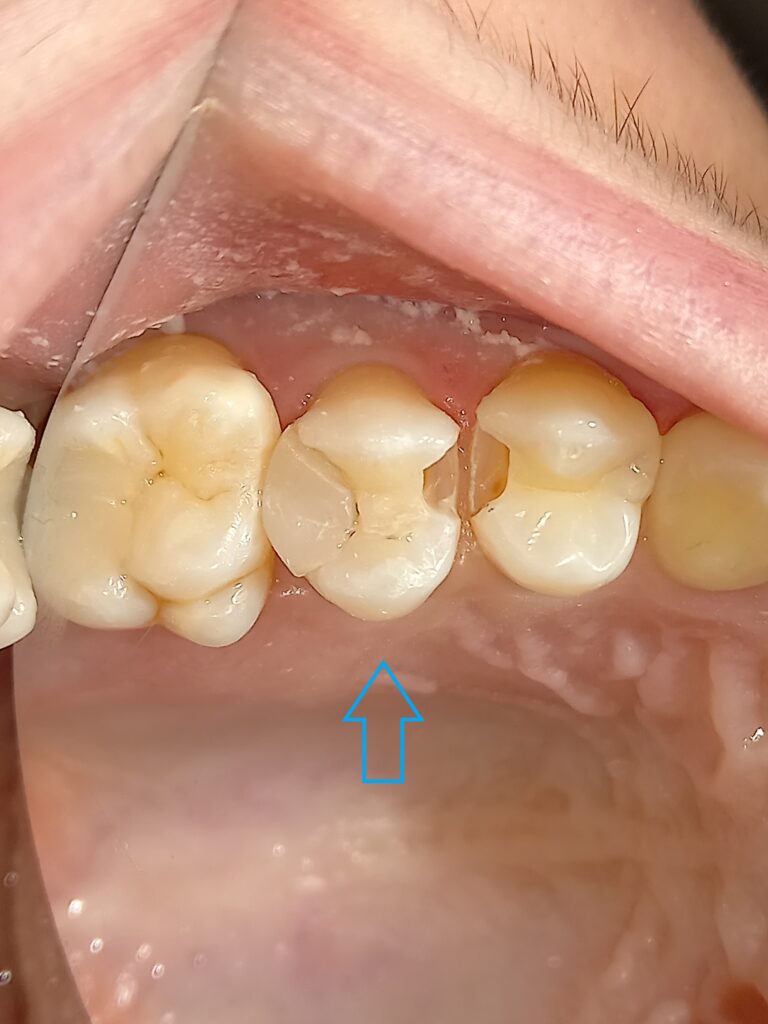

Αρχική κλινική εικόνα με το παλιό σπασμένο σφράγισμα